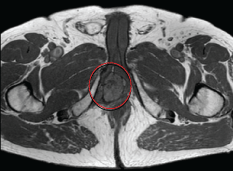

We present the case of a 71-years-old Caucasian male, with a past medical history of hypertension, Benign Prostatic Hyperplasia (BPH) and previous inguinal hernia repair. In November 2002, he underwent a laparoscopic left radical nephrectomy for a 10-cm CRCC of the left kidney with perirenal fatty tissue involvement and thrombosis of the left renal vein (pT3b N0). Patient was followed up regularly on the basis of the EAU guidelines on renal cancer. After a 14-year follow-up he presented a painless, irregular, solid mass of the perineum. MRI scan of the pelvis and perineum revealed a dishomogeneous solid expansive lesion with polylobate profiles of 52 × 58 mm, that originated from the crus of right corpus cavernosum: The mass was placed posteriorly to the base of the penis and strictly related to the internal profile of the right ischiopubic branch with partial compression and dislocation to the left of the anal canal and of the corpus spongiosum of the urethra (Figure 1a and Figure 1b). Moreover, the mass reached the limit of the membranous urethra. A trans-perineal ultrasound guided biopsy of the lesion was performed, and the pathological result showed a metastasis of CRCC. A multi-disciplinary meeting was scheduled. The patients presented favorable prognosis according to Heng and Memorial Sloan-Kettering Cancer Center (MSKCC) criteria and would have benefited from surgical resection of this single metastasis. In order to reduce surgical risk during the exeresis of the mass, the patient was treated with 4 cycles of pazopanib, as presurgical modality. Adverse effects were G1 increase in blood pression and grade 2 diarrhea symptoms. In April 2017, a follow-up-scheduled MRI scan demonstrated volumetric a 30% reduction of the perineal lesion (Figure 2a and Figure 2b). Thus, in June 2017, this patient underwent metastasectomy of the perineal mass by a median perineal access. The mass was smoothly dissected from the corpus cavernosum and the corpus spongiosum of the urethra (Figure 3a, Figure 3b and Figure 3c). The final pathological report revealed metastatic carcinoma from the right corpus cavernosum, compatible with RCC dissemination, and with negative surgical margins. According to complete resection, no TMT was proposed after surgery. At 12-month follow-up, the patient is in general good health status, and total body CT scan showed no recurrences.

Figure 3: a,b) The mass was dissected from the corpus cavernosum and the corpus spongiosum (white arrow points the mass and its relations to corpus cavernosum (a), and corpus spongiosus (b); c) Surgical field after complete resection of the metastasis. View Figure 3